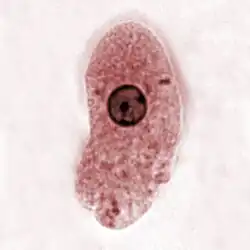

Entamoeba histolytica (Magna-Form, | ||||||||||||

Merkmale

Entamoeba histolytica ist ein einzelliger eukaryoter Organismus ohne Mitochondrien (stattdessen mit Mitosomen), lebt anaerob, ernährt sich heterotroph und ist zur Phagozytose anderer Zellen, beispielsweise von Bakterien, fähig. Wegen seiner wandelbaren Körperform, verbunden mit einer Fortbewegung über Pseudopodien (Scheinfüßchen), wird er – wie auch verschiedene andere Arten – als Amöbe bezeichnet. Dieser amöboide Protist gehört zur Gattung Entamoeba. E. histolytica durchläuft in ihrem Lebenszyklus zwei Stadien: das einer unbeweglichen Zyste und das eines Trophozoiten, der hauptsächlich den menschlichen Darmtrakt besiedelt. Die Minuta-Form des Einzellers wird 10 bis 15 Mikrometer groß, die Magna-Form 25 bis 40 Mikrometer. Die gebildeten Zysten sind tetraploid, sie enthalten im reifen Zustand vier Zellkerne und erreichen eine Größe von rund 20 Mikrometern.[1]

Bei 10–20 % der Infizierten entwickeln sich Zeichen einer Erkrankung. Bei den besiedelnden Trophozoiten lassen sich zwei Formen unterscheiden, die kleine Minuta- und die größere Magna-Form. Minuta-Formen gleichen anderen, nicht pathogenen Entamoeba-Arten und leben im Dickdarmlumen des Wirts auf intakter Schleimhaut; diese Art der Kolonisierung ruft zumeist keine Symptome hervor.

Trophozoit, E. histolytica -